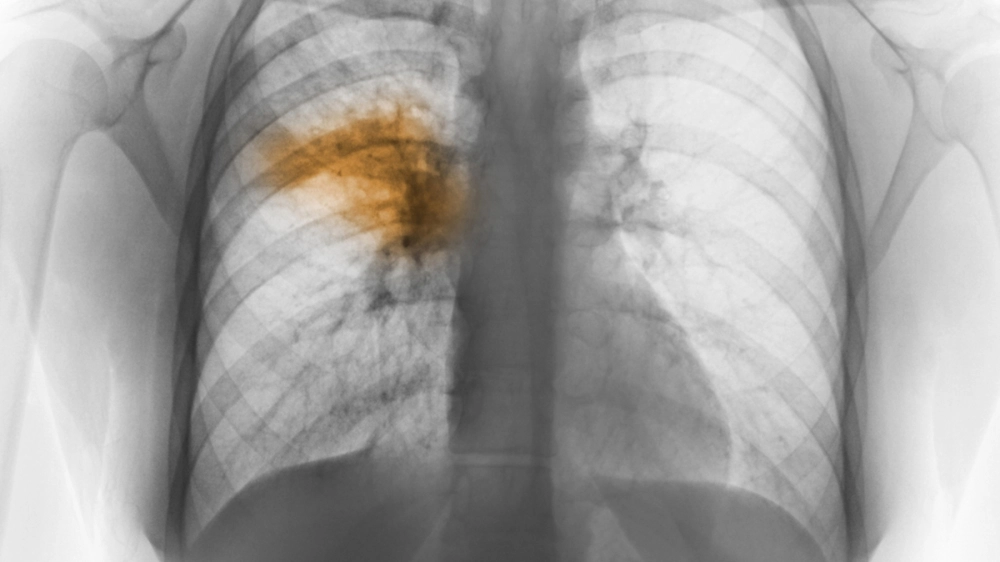

Hình ảnh chụp X-quang phổi của bệnh nhân bị viêm phổi

Hình ảnh tổn thương thùy phổi khi chụp X-quang phổi